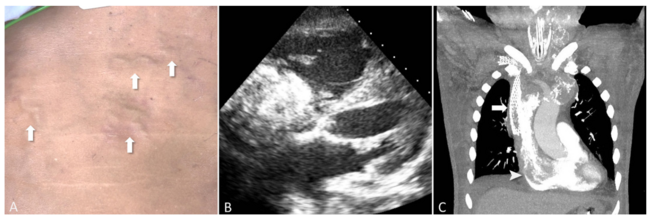

A 72-year-old man presented with altered consciousness. His past medical history included left renal cell carcinoma status post nephrectomy 3 years earlier, end-stage renal disease with regular hemodialysis, and central venous obstruction with stenting at the right subclavian vein and superior vena cava 8 months earlier. He was intubated and placed on a mechanical ventilator and inotropes for managing respiratory failure and shock. Physical examination revealed jugular vein enlargement and cutaneous varices over the chest wall (Figure 1A, arrow). The varices were engorged and then vanished during the respiratory cycle (Video Series). Transthoracic echocardiography revealed a 4.5- × 5.7-cm2 heterozygous mass in the right atrium (Figure 1B and Video Series). Computed tomography showed a large, calcified thrombus from the central veins to the right atrium (Figure 1C). During the inspiratory phase, the mechanical ventilator inflated the lung, resulting in positive pressure in the right ventricle that limited ventricular dilation during diastole. The right atrial mass also hindered blood flow into the right ventricle and caused blood to flow back into the peripheral venous system. This could cause obstructive cardiogenic shock and fluctuating cutaneous varices (Video Series). The patient refused further intervention and died from multiple organ failure. The unusual phenomenon provided a clue for a huge right atrial mass in dialysis patients.